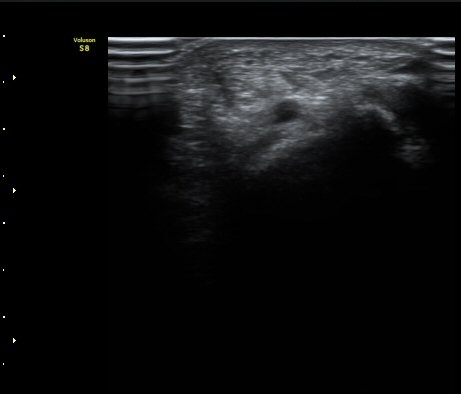

[ÆÈ²ÞÄ¡] ¿»ó ÈÄ ¹ß»ýÇÑ ¿ä°ñ½Å°æ ¸»´Ü °¨°¢½Å°æ ºÐÁö º´Áõ